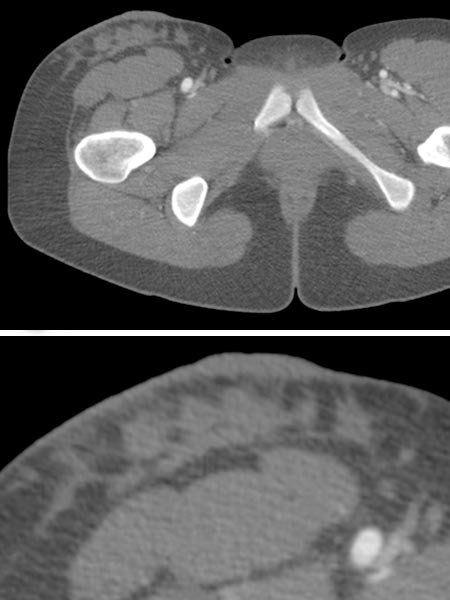

In der entsprechenden Computertomographie ist die LM mit ihrer Flüssigkeitseinlagerung und bindegewebigen Komponente etwas hyperdenser als das umgebende subkutane Fettgewebe dargestellt, der Weichteilkontrast ist schlechter als in der MRT. Es findet sich in der CT auch keine KM-Anreicherung. Beachte in der Ausschnittsvergrößerung (unteres Bild) die Verdickung der Haut durch die kutanen mikrozystischen Anteile der LM.